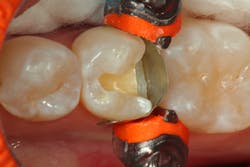

A critical part of the success of the restorative process is an excellent matrix system. We have had many years of great results using a sectional matrix system (ComposiTight, Garrison). The sectional matrix is anatomical in its design, helping create a more anatomically correct proximal contour. The ring is designed not only to get great adaptation of the matrix, but also to provide additional proximal separation in addition to what the wedge provides (figure 2).